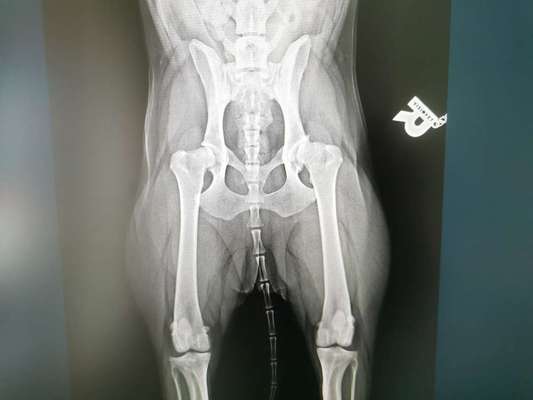

Mein Hund hat HD und Arthrose, im rechten Hinterfuss Endstadium und links hinten mittleres Statium. Kann man da mit ACP( Autologes Konditioniertes Plasma) oder PRP ( Platelet Rich Plasma) behandeln?